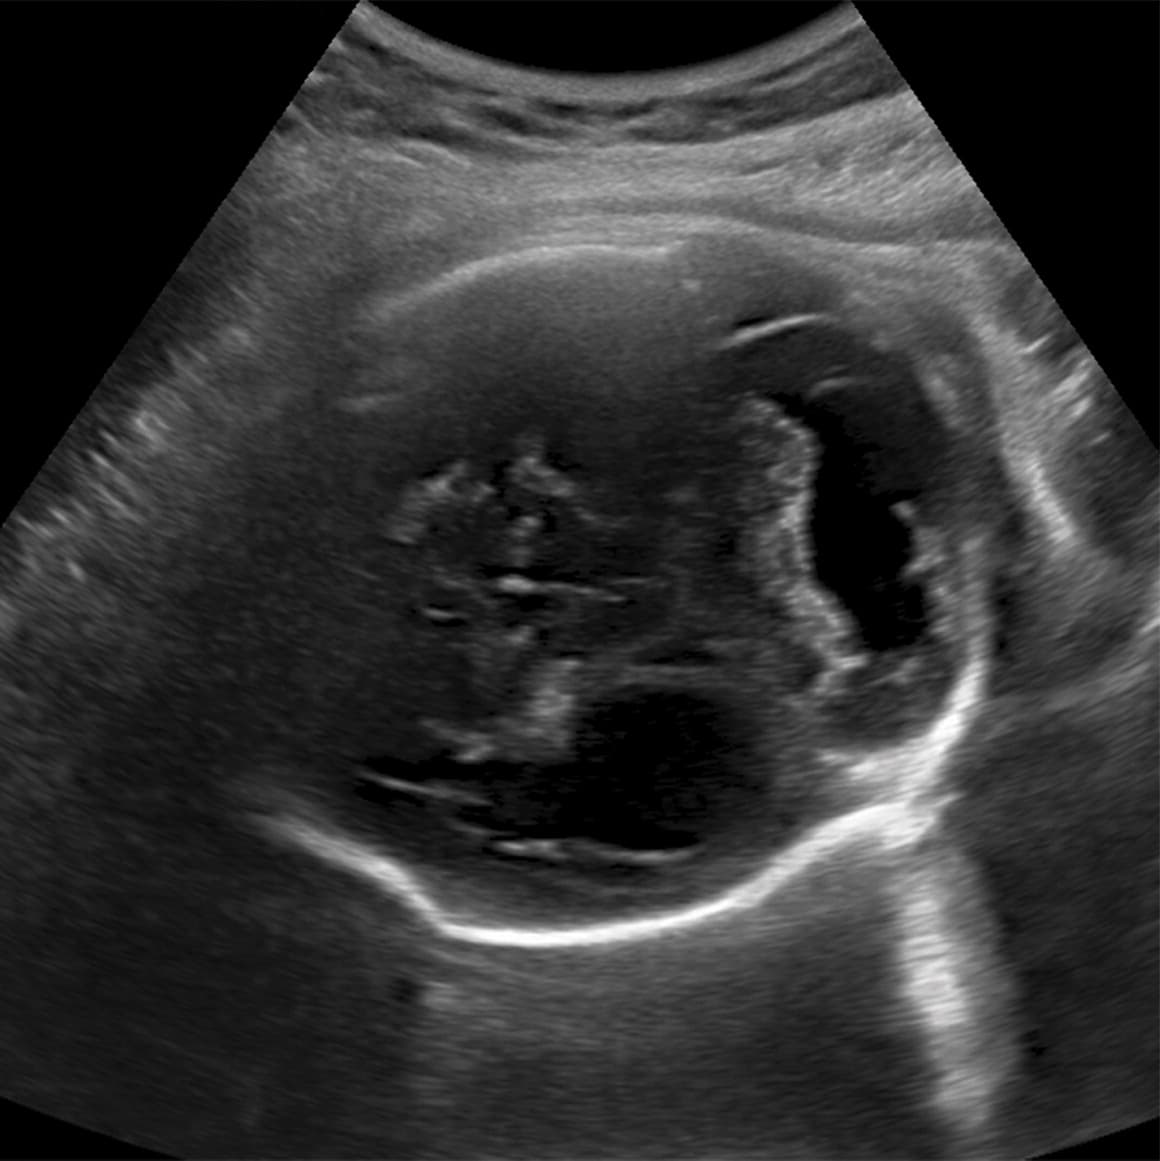

A las 17 semanas el tamaño de la circunferencia de la cabeza del feto estaba dentro del rango normal.

Radiology.

A partir de la semana 21 empezaron a verse signos de que el cerebro del feto no crecía al ritmo debido.